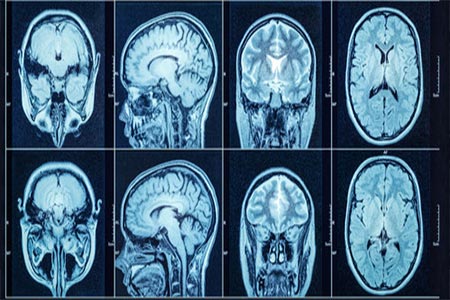

Altogen Biosystems announced that its Nanoparticle-based In Vivo Transfection Reagent was used for effective overcoming blood-brain barrier and successful transfection of glioblastoma tumor cells with both plasmid DNA and siRNA molecules. Altogen Labs mouse orthotopic PDX glioblastoma xenograft model was used for the study. This xenograft model reproduce glioblastoma histologic complexity and many biological behaviors (angiogenesis, brain invasion, and resistance to therapy). Altogen Labs research study demonstrated functional cargo delivery of both siRNA and DNA (3.72Kb) through the blood–brain barrier, as well as high transfection efficiency and reproducibility. Nanoparticle-based In Vivo Transfection Reagent is available as reagent-grade that is commonly used for preclinical research studies, as well as GMP grade product manufactured for clinical research applications. Altogen's nanoparticle in vivo transfection reagent was referenced in over 40 research publications for effective in vivo delivery of biomolecules, however Altogen scientists still had to develop modified in vivo transfection protocol to enable brain-targeted delivery.